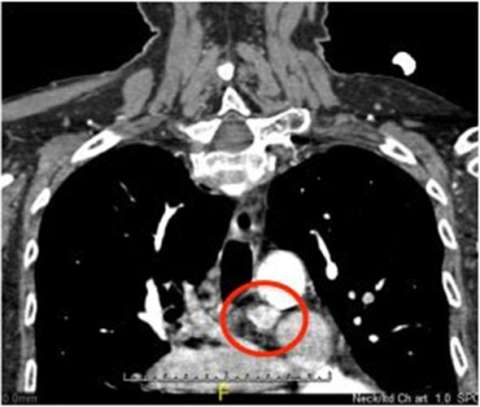

The parathyroid CT, on the other hand, shows a lot more detail and helps us see parathyroid glands even when they're only very slightly enlarged. The parathyroid CT uses a different kind of chemical that isn't taken up by the parathyroid glands. Lymph nodes and thyroid tissue can also look like parathyroids in this scan. For that reason, even though there is more detail, it takes experience to read the scan correctly.

Parathyroid CT Scan